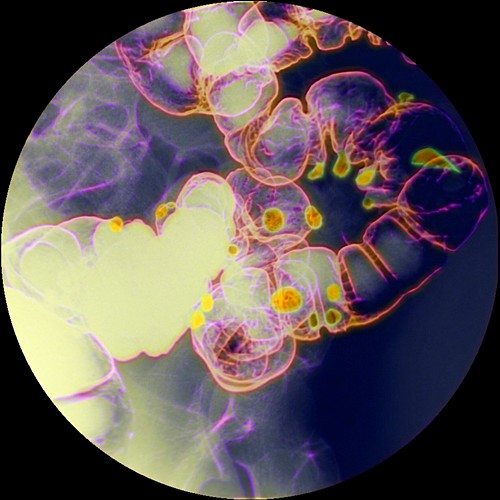

From pixels.com

Diverticulitis Photograph by Pixologicstudio Pixels Flaxseed Diverticulitis no specific foods are known to trigger bouts of diverticulitis symptoms, also called attacks. Even though about 58% of. And no special diet has. Having had an episode of diverticulitis in the past. Diverticulitis (also referred to as a. diverticulosis happens when small pouches (diverticula) form in the walls of the colon. discover if chia and flax. Flaxseed Diverticulitis.